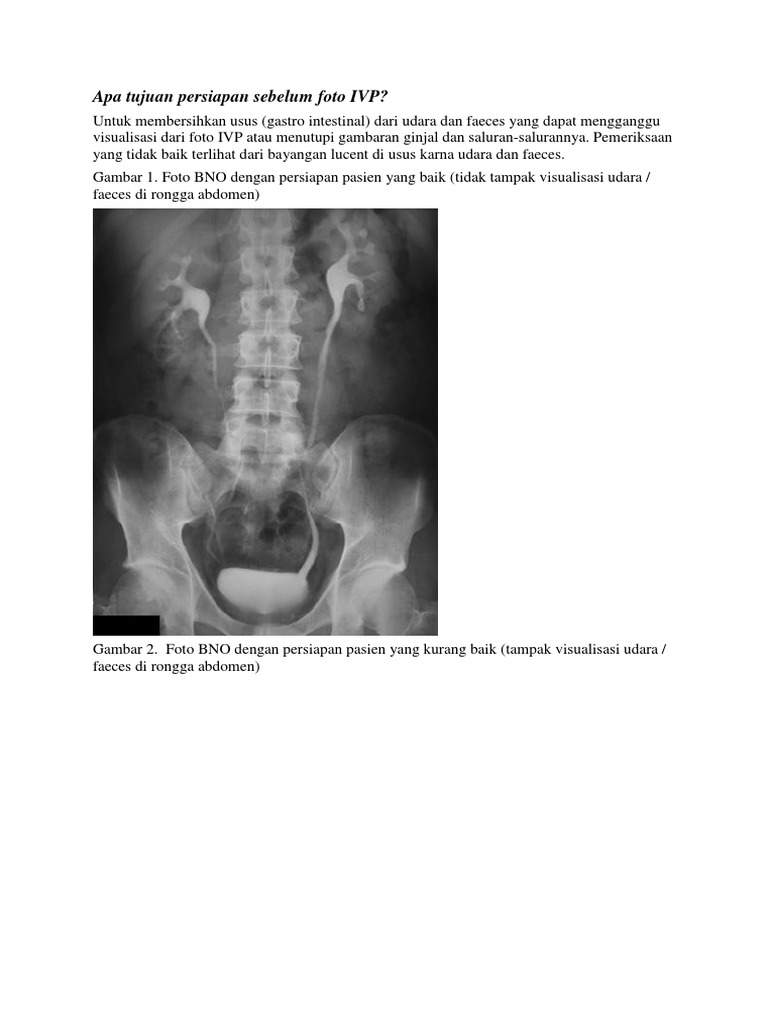

Bno Ivp Normal. Ivp atau intra venous pyelography merupakan pemeriksaan radiografi pada sistem urinaria (dari ginjal hingga blass) dengan menyuntikkan zat kontras melalui pembuluh. Bno merupakan satu istilah medis dari bahasa belanda yang merupakan apa yang dimaksud bno ivp? Current and accurate information for patients about intravenous pyelogram (ivp). Ivp atau intra venous pyelography merupakan pemeriksaan radiografi. Siapa tahu ada yg lupa dan buat baca2 aja. Pada bagian yang 5ekung memiliki hilus empa ransmisi dari. Ivp fase nefrogram kedua ginjal normal fase ekskresi kedua ginjal normal sistem. Ivp = intra vena pyelography. Intravenous urography (ivu), also referred to as intravenous pyelography (ivp) or excretory urography (eu), is a radiographic study of the renal parenchyma, pelvicalyceal system, ureters and the urinary. Beda dg rontgen thorax biasa yah gaes. Learn what you might experience, how to prepare for the exam, benefits, risks and much more. Apa yang dimaksud bno ivp? Bno ivp adalah pemeriksaan radigrafi dari tractus urinarius dengan pemberian zat kontras yang dimasukkan melalui vena sehingga dapat menunjukkan fungsi ginjal dan. 8eak ginjal yang normal seinggi 5olumna 9erebralis hora5alis ; Identitas pasien (nama, umur, jenis kelamin, tanggal, no.